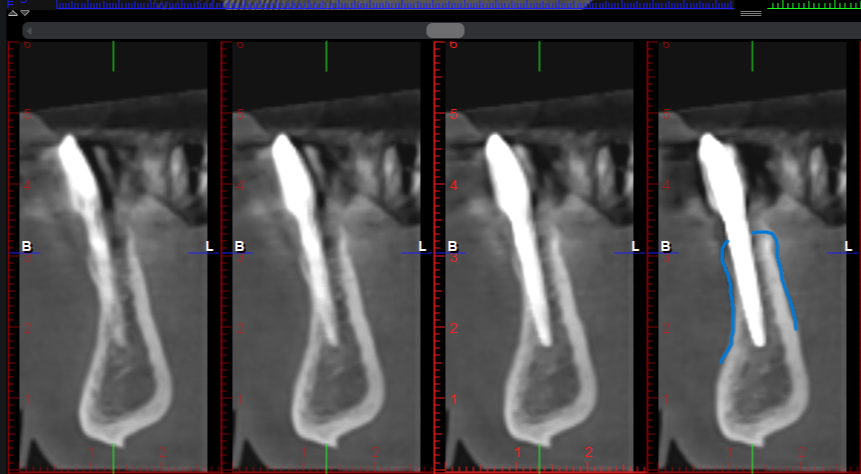

Tras realizar un diagnóstico por imagen en 3D, observamos la pérdida total de la cortical vestibular y lingual a nivel del 4.1 (Figura 7 -8).